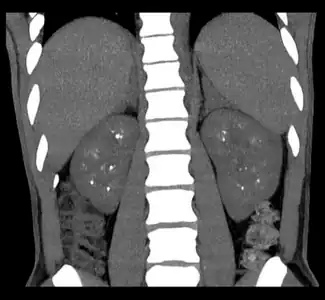

- Non-contrast coronal CT depicts nephrocalcinosis.

Nephrocalcinosis is diagnosed for the most part by imaging techniques. The imagings used are ultrasound (US), abdominal plain film and CT imaging.[11] Of the 3 techniques CT and US are the more preferred. Nephrocalcinosis is considered present if at least two radiologists make the diagnosis on US and/or CT. In some cases a renal biopsy is done instead if imaging is not enough to confirm nephrocalcinosis. Once the diagnosis is confirmed additional testing is needed to find the underlying cause because the underlying condition may require treatment for reasons independent of nephrocalcinosis.[11] These additional tests will measure serum, electrolytes, calcium, and phosphate, and the urine pH.[11] If no underlying cause can be found then urine collection should be done for 24 hours and measurements of the excretion of calcium, phosphate, oxalate, citrate, and creatinine are looked at.[11]